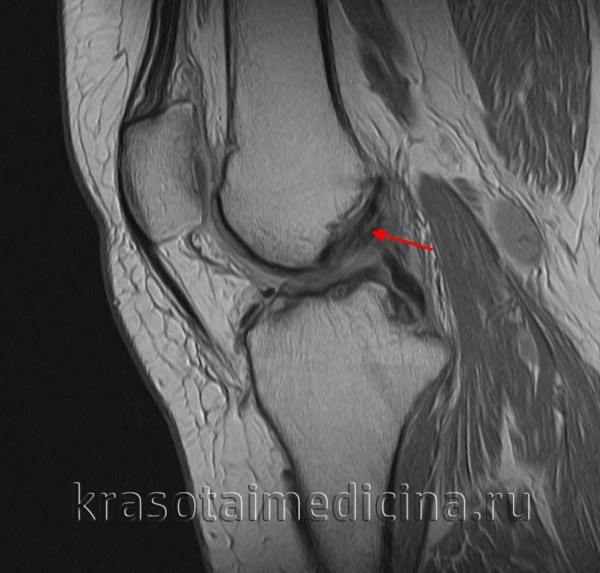

МРТ коленного сустава. Повреждение (отек, разволокнение, частичный разрыв) передней крестообразной связки.